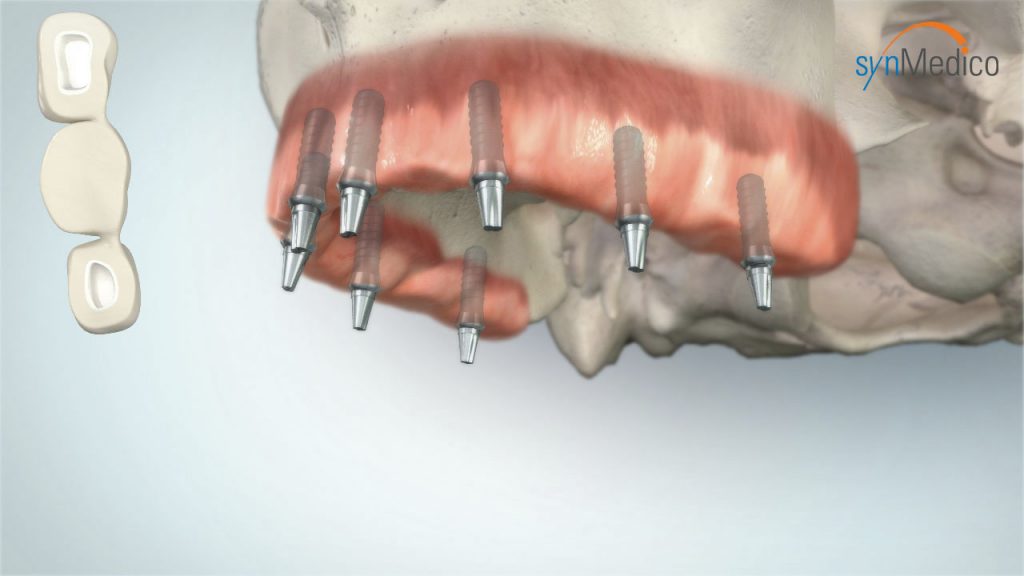

Zahnloser Kiefer

Auch ein zahnloser Kiefer kann mit Implantaten komfortabel versorgt werden. Bereits bestehender Zahnersatz gewinnt auf Implantaten neuen, verbesserten Halt. Das Gesichtsprofil bleibt erhalten, Essen und Lachen ist kein Problem mehr, die Aussprache wird deutlicher. Der Patient kann sich auf einen wirklich funktionierenden Zahnersatz verlassen.